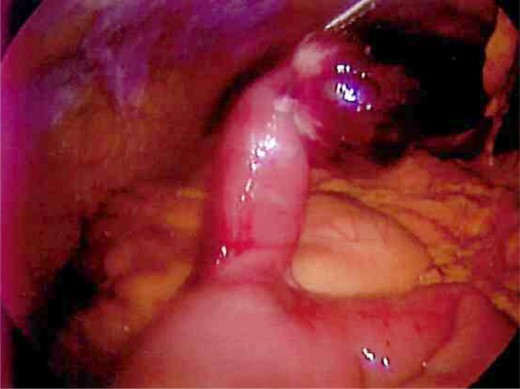

Laparoscopy was performed and a large Meckel's diverticulum was identified ∼30 cm proximal from the ileocecal valve. It had twisted 360° and was swollen and gangrenous at the distal half (Fig. 1). The tip of the diverticulum contained a 3-cm long mesodiverticular band that was attached to the mesentery of an adjacent loop of terminal ileum (Fig. 2). The mesodiverticular band was surgically divided, and the diverticulum was then de-torsed revealing a normal appearing base (Fig. 3). The diverticulum was excised along its base using an endoscopic stapler (Fig. 4). The surgery was completed with an appendectomy. On postoperative day one, the patient was doing well and was discharged home.